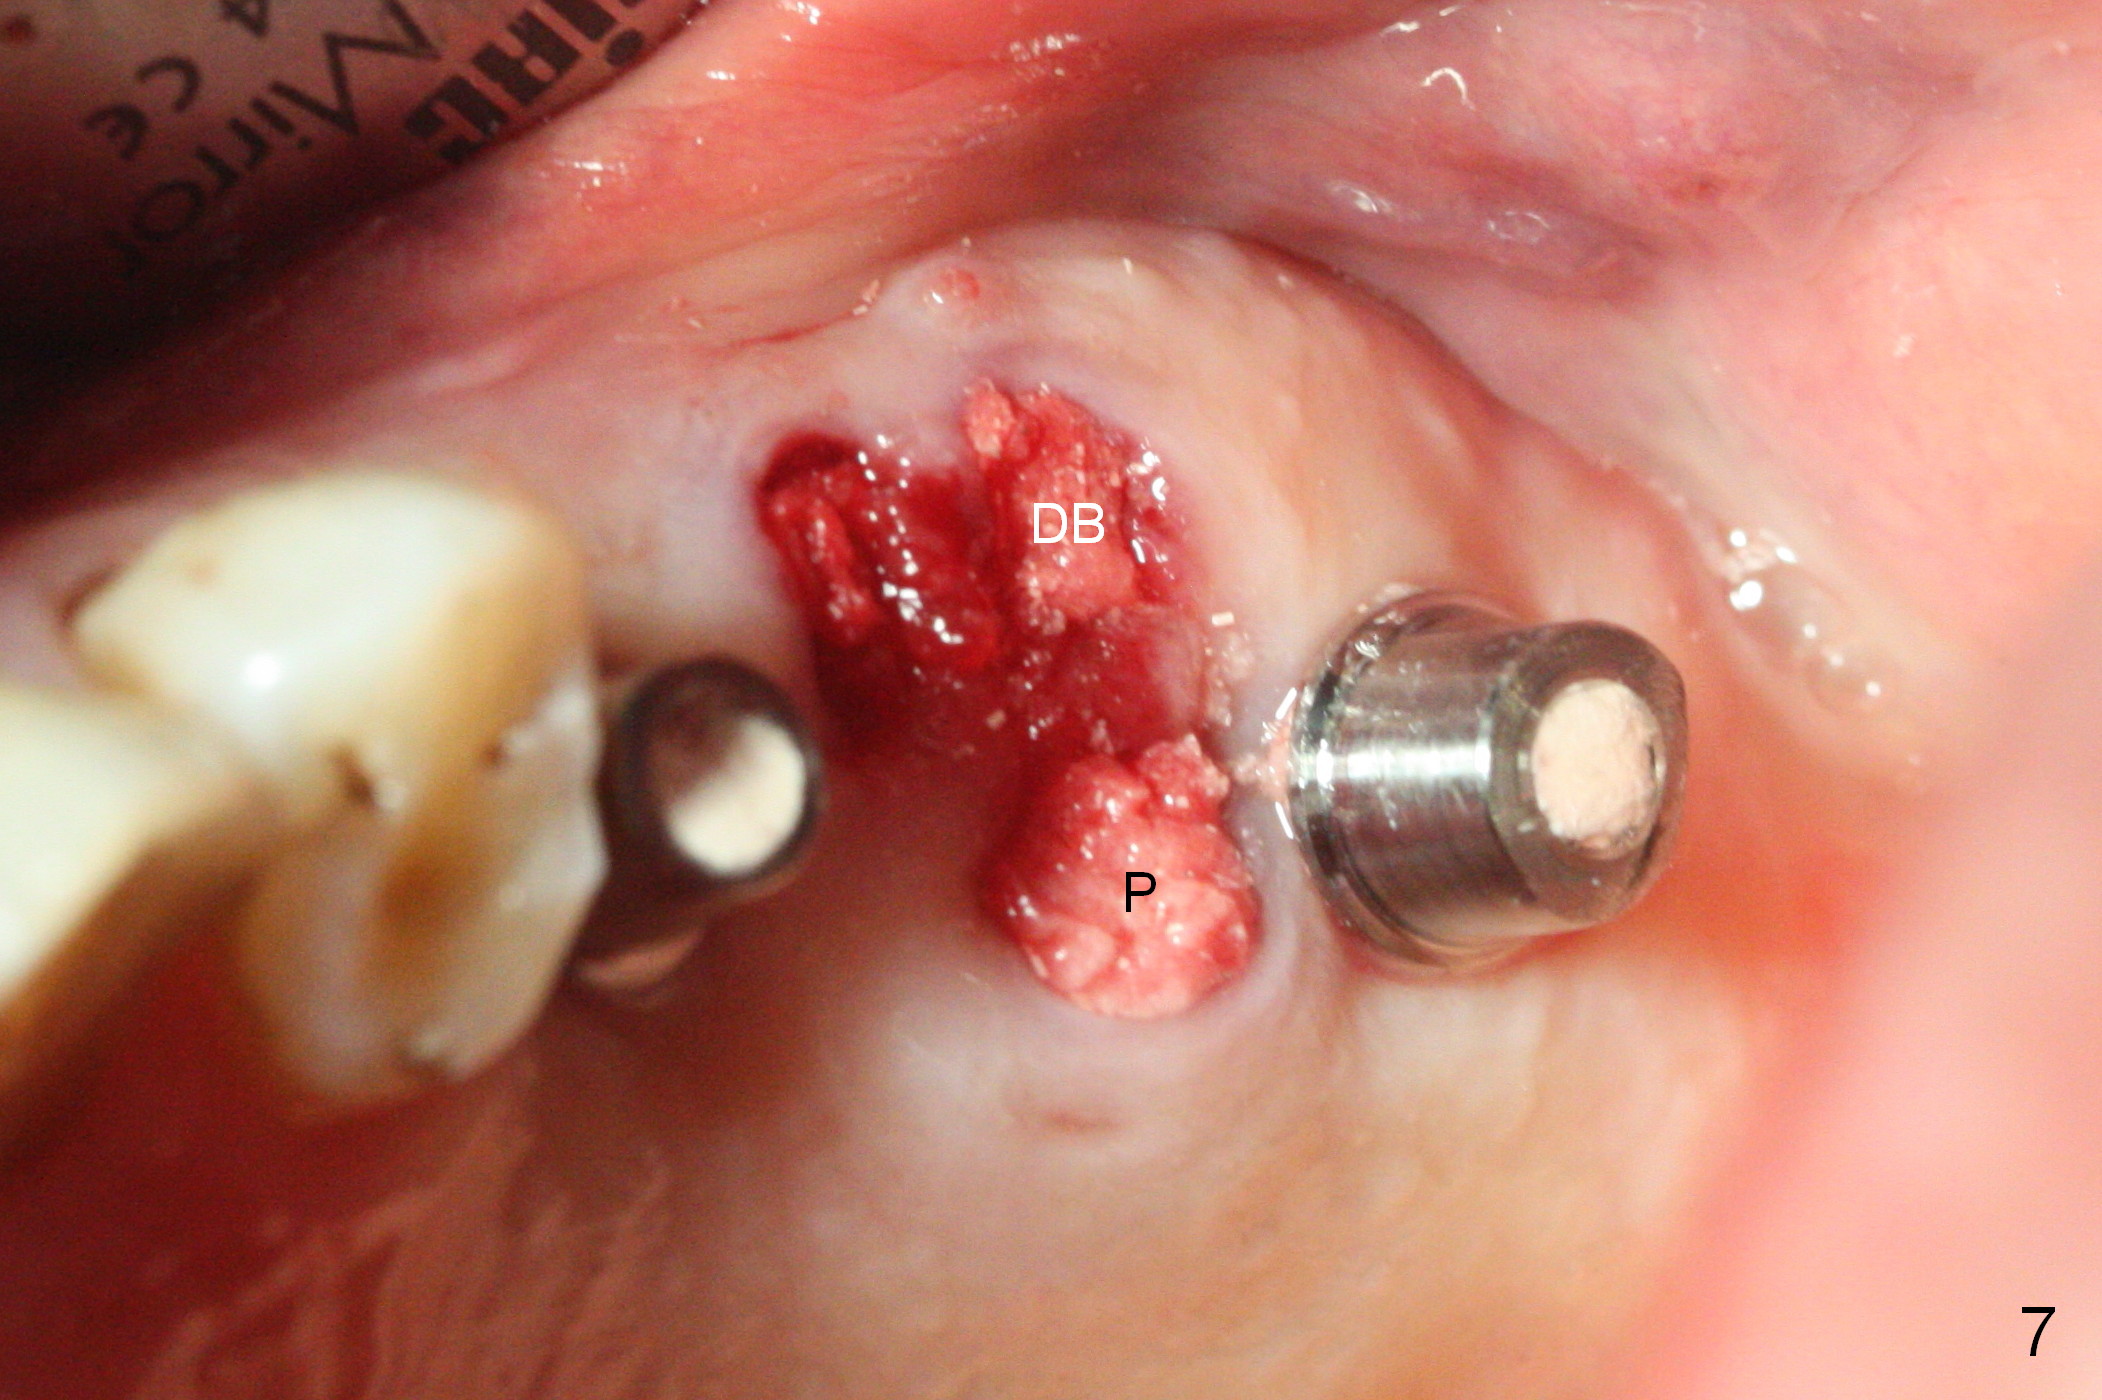

After placement of the remaining graft into the palatal (Fig.6,7 P) and distobuccal (DB) sockets of #14 and collagen plug into the 3 sockets of #14, abutments change to those with cuffs 1 mm shorter. The abutments are used to hold an immediate provisional bridge in place. The latter keeps the collagen plug and graft in place.

The fistula buccal to #14 remains 1 week postop (Fig.7) and disappears 1 months postop. The fistula does not re-appears 3 months postop with the implants at #13,15 apparently osteointegrated (Fig.8). With relining #13-15 provisional with increased vertical height (Fig.11), the patient has bilateral posterior contact (Fig.9), while the lower incisors do not contact the cinguli of the upper incisors (Fig.10 *). The space between the tooth #12 and the pontic #21 is unfavorable for posterior occlusal stability (Fig.11 *). Porcelain is chipped off the buccal surface of the pontic (Fig.12 *). If the patient does not afford an implant at #21 with redo crowns at #20 and 22 (Fig.13), what else could be done? He will return for #15 implant placement 4 months post socket preservation.